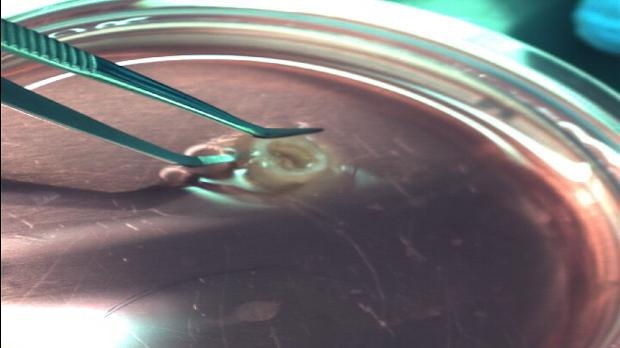

Sabancı Üniversitesi Nanoteknoloji Uygulama ve Araştırma Merkezi’nde dünyanın ve Türkiye’nin ilk 3 boyutlu biyoyazıcı ve insan canlı hücreleri kullanılarak aort damarı üretildi. Üniversitenin Mühendislik ve Doğa Bilimleri Fakültesi Üretim Sistemleri Programı öğretim üyesi Doç. Dr. Bahattin Koç ve ekibi çatallanan damarları üretme çalışmaları da yapıyor.

Bir aort 3 boyutlu yazıcıyla yaklaşık 1.5-2 saatte elde edilebiliyor. Üretim adım adım şöyle gerçekleşiyor: Aort damarı doku örneğinin MR (manyetik rezonans) taramasıyla dataları çıkarılıyor. Yine ekibin geliştirdiği algoritmalar kullanılarak üretilecek dokunun anatomisine göre hücrelerin basım yolları en uygun şekilde hesaplanıyor.

Aynı zamanda hücreleri desteklemek için destek yapılar belirleniyor. Bu çalışmanın diğer yapılanlardan en büyük farkı, tüm hücrelerin tamamen birbirini desteklemiş şekilde dokunun üç boyutlu anotomisine uygun olarak belirlenmesi.